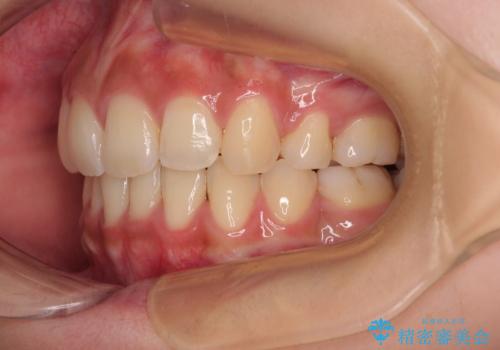

- 前歯の突出感とデコボコを気にして来院された患者様です。

奥歯の噛み合わせをみると、上顎歯列が全体的に前突している状態であり、この咬み合わせのまま歯列を整えると出っ歯になってしまう可能性がありました。

上下の前歯が接触する仕上がりとなったので、横顔の印象が大幅に改善されました。